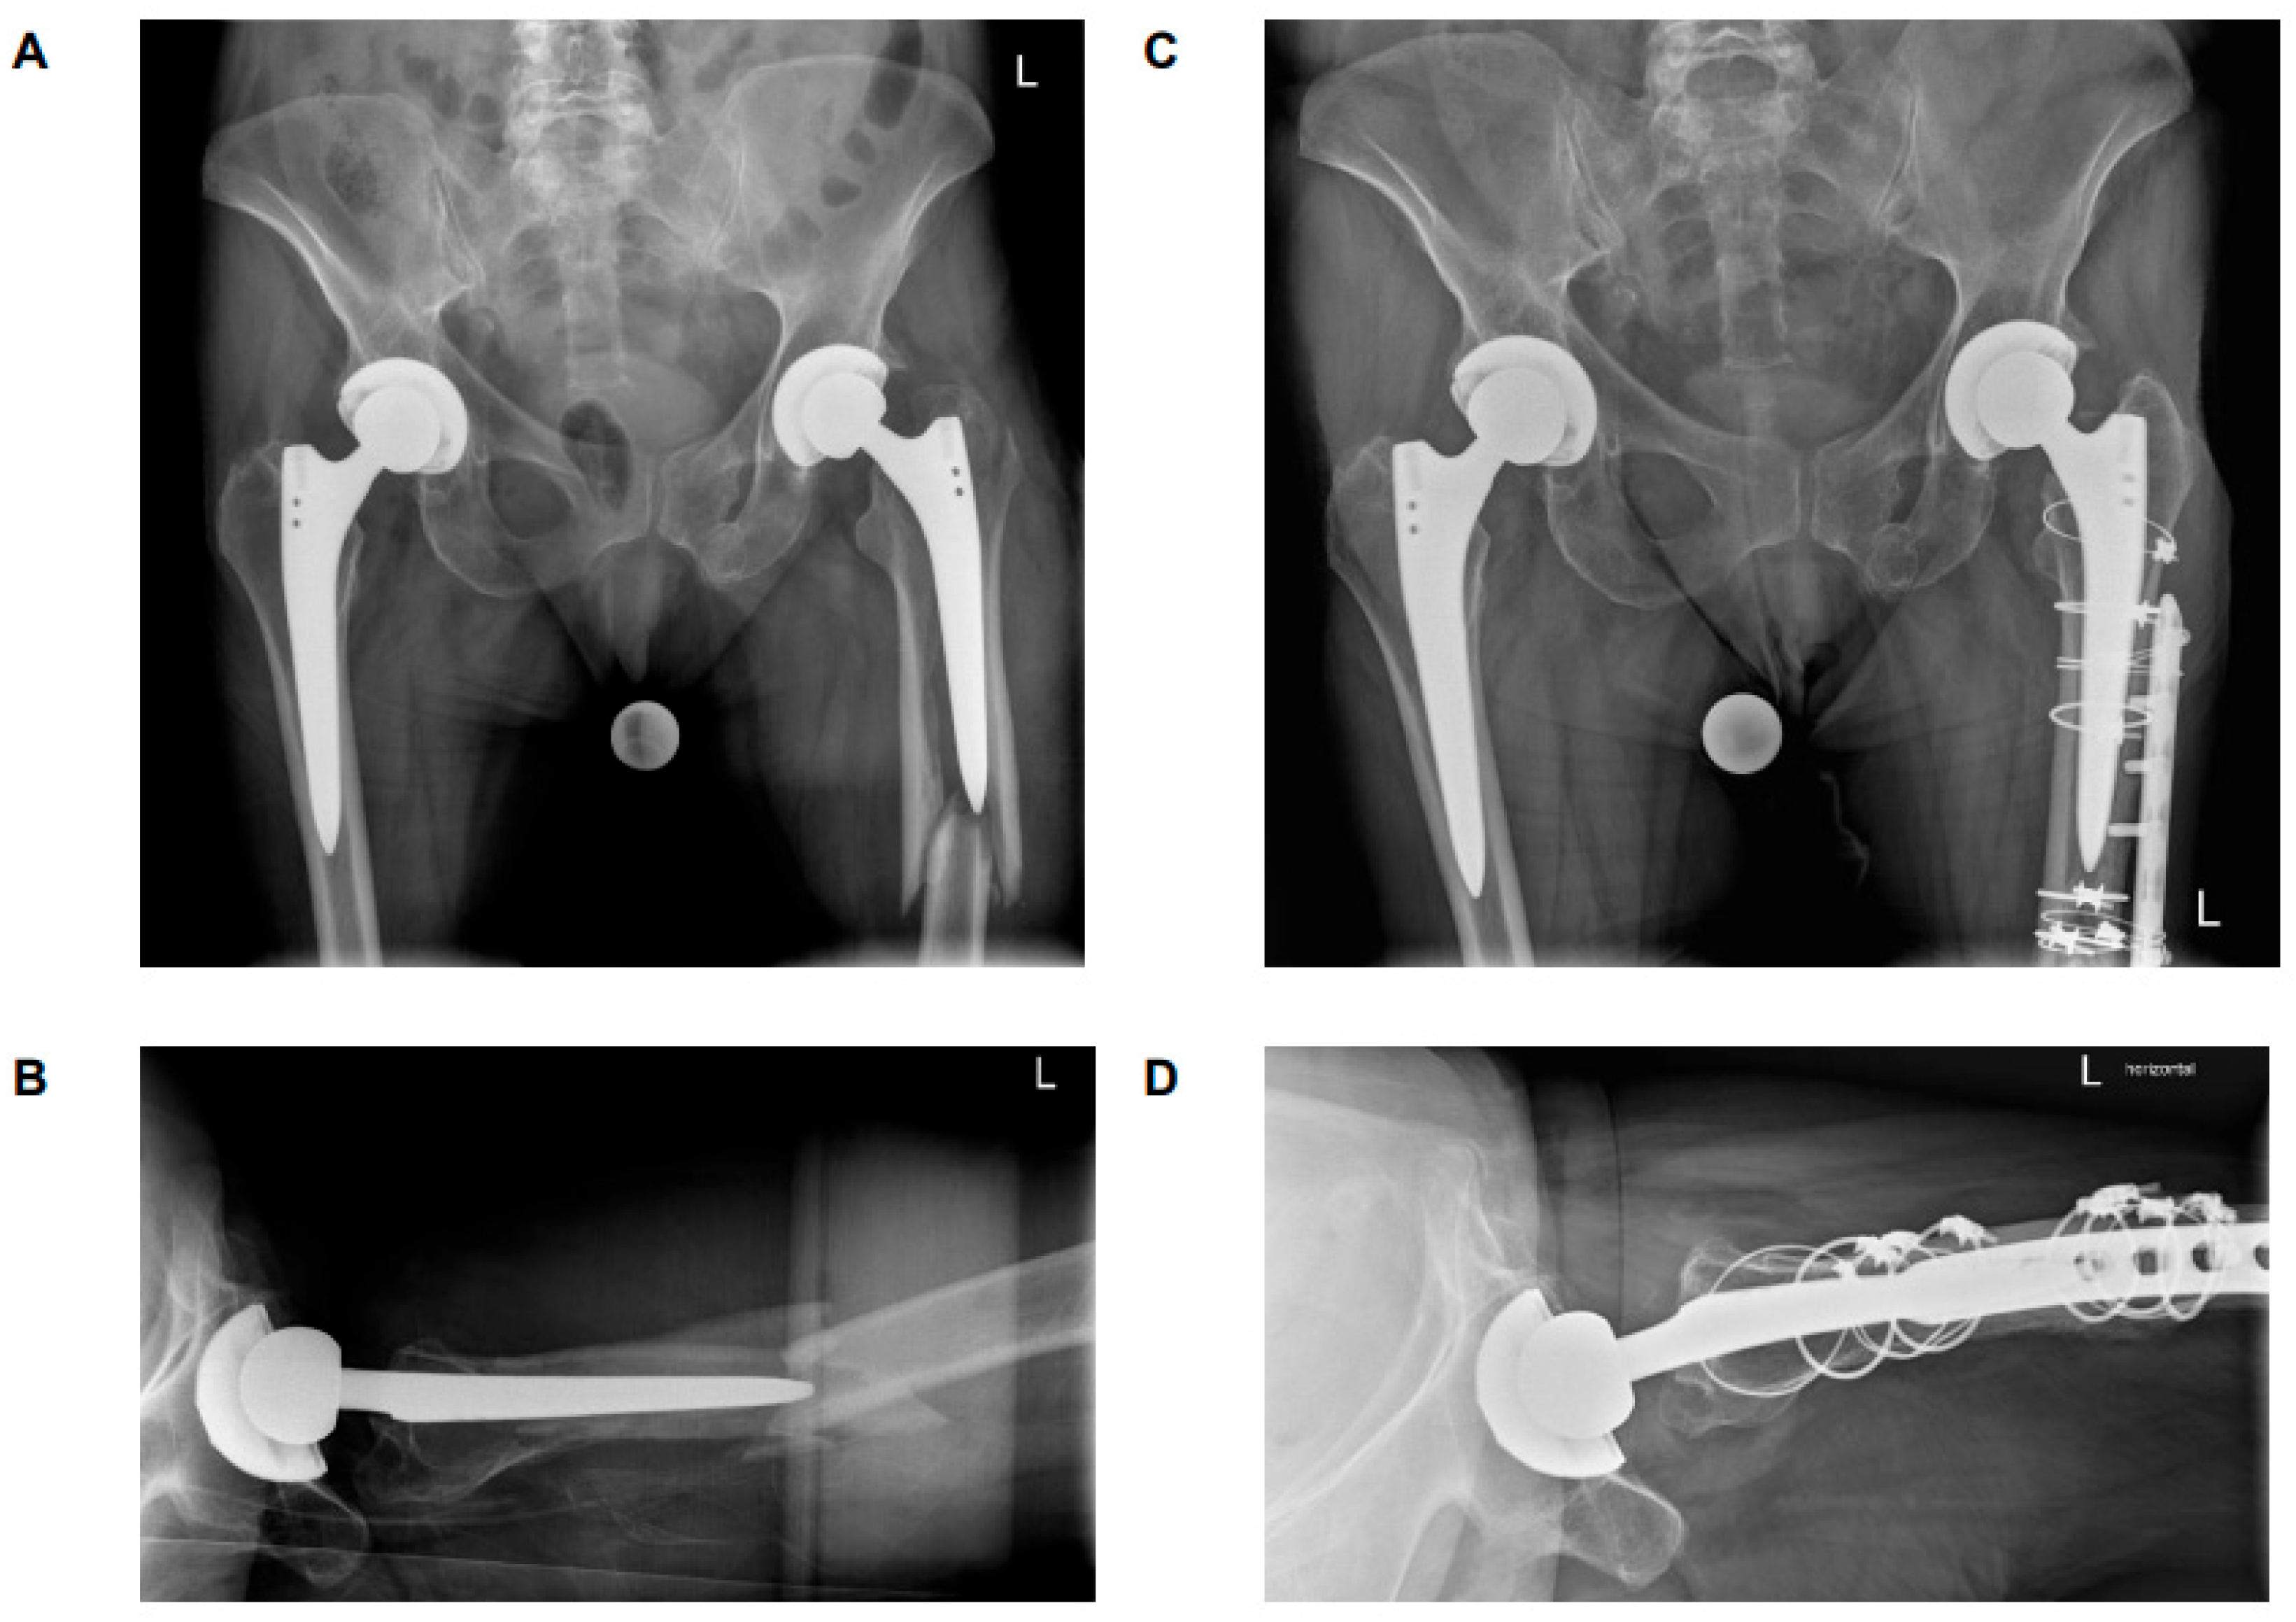

4.1. B2 ‘Stable’ Stems

4.2. B2 ‘Loose’ Stems